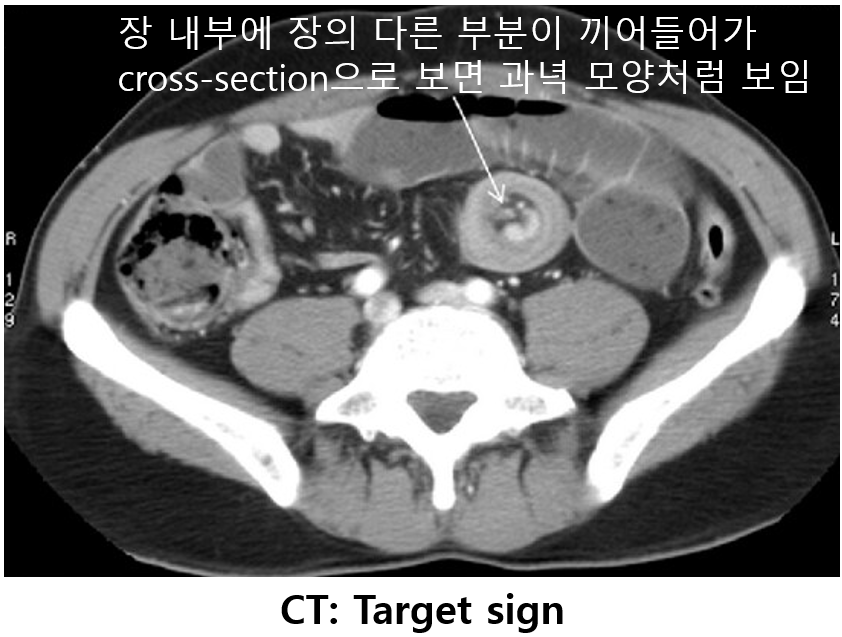

2) 진단: CT상 target sign 등